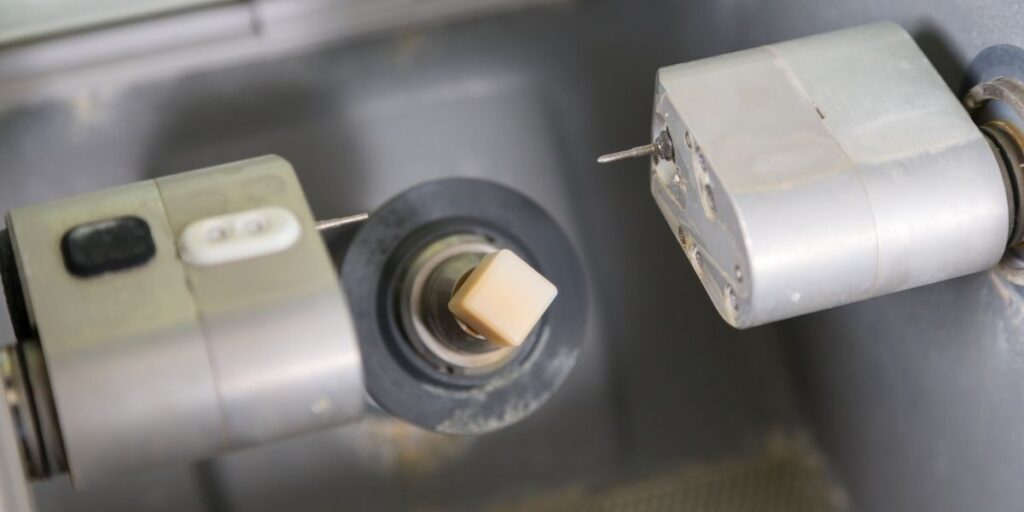

Our product engineers took complete ownership on development. We extracted models from patient scans to create the right dental implants that took care of the sockets in the patients. By working hand-in-hand with the R&D team, as well as our cross-functional teams of mechanical designers, analysts, and engineers, we pushed through the engineering hurdles and used 3D printing (additive manufacturing) to develop these dental implants.

Successful prototyping and testing

Another major focus was ease-of-use of these special dental implants by the dental surgeons. We sourced the needed materials from our network of reliable suppliers, and started mock testing. Even though we were working with a smaller sampling due to the constraints of this project, we achieved the right solution with our expertise and experience.